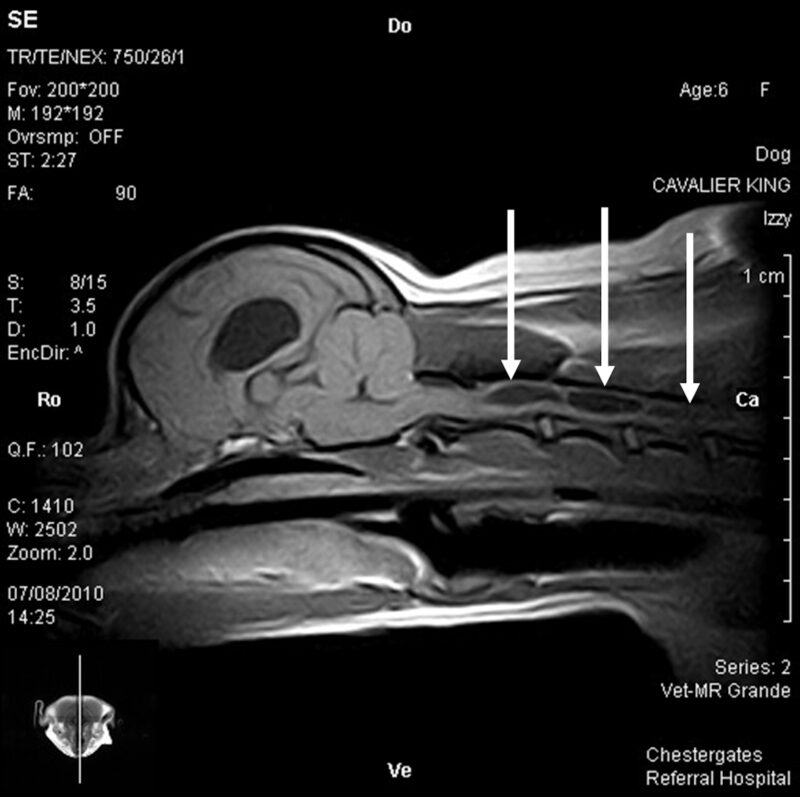

Der CKCS zeigt aber wie bei MMVD eine weitere polygenetisch vererbte Erkrankung: Die Syringohydromyelie (SHM), häufig in Verbindung mit einer Verlängerung des kaudalen Kleinhirnwurmanteils in Richtung des Foramen magnum (Chiari-ähnliche Missbildung). Betroffene Hunde weisen häufig eine Erweiterung des medullären Zentralkanals mit teilweise erheblicher Verdrängung des Rückenmarkgewebes nach peripher. Dabei kann es zu einem Einbruch unter Verletzung des auskleidenden Ependyms in die Graue Substanz kommen, wodurch die sekundären nozizeptiven Neurone und die aszendierenden spinothalamischen Nervenbahnen weiter komprimiert werden. Daraus ergibt sich häufig, wenn auch nicht immer, das klassische klinische Bild des kratzenden Cavaliers. Bei Aufregung, Erwachen und Stresssituation steigt der Blutdruck physiologischerweise an und sorgt für eine amplituden-erhöhte Pulswelle im Liquorsystem. Der Flüssigkeitsdruck auf die bereits vorgeschädigten Neuronen sorgt für eine Signalentstehung im Myelon, das in Richtung Thalamus vom Myelon weitergeleitet wird. Der betroffene Hund empfindet ein Jucken bis zum Brennen im Bereich des assoziierten Dermatoms, häufig im Hals-Schulterbereich; das klinische Bild des „air-guitar“-spielenden Hundes entsteht, häufig ohne wirkliche Berührung der Haut. Obwohl inzwischen fast alle CKCS mit der Chiari-ähnlichen Missbildung geboren werden und ein pathogenetischer Zusammenhang wahrscheinlich erscheint, z.B. durch Verschluss des Foramen magendie und Hemmung des Rückflusses aus dem Zentralkanal in den vierten Ventrikel, sind andere Theorien zur Entstehung der SHM aufgeworfen worden: z.B. frühzeitiger Verschluss und daher Verkürzung der Schädelbasis (Schmidt et al., 2013), atlanto-okzipitaler Overlap (Marino et al., 2012), Ventrikulomegalie (Territo e al., 2022). Einzeln genommen gibt es ähnliche Befunde auch bei anderen Rassen (z.B. Zwergspitz, Yorkshire Terrier, Chihuahua), die dort allerdings nicht immer zur Ausbildung einer SHM führt. Die pathogenetische Ratlosigkeit wird dadurch noch vergrößert, dass es auch bei den CKCS sehr selten Fälle von zervikaler Hyperästhesie ohne erkennbare Expansion des Zentralkanals gibt. Besonders Chihuahua zeigen mit einer ausgeprägten SHM entlang des gesamten Myelons eher spinale Ataxien ohne Hyperästhesie.

Die MRT-basierte Untersuchung wird in Sedation und mit drei Kurzsequenzen durchgeführt. Nach fast 700 Scans konnten wir zeigen, dass die Zahl der mit SHM untersuchten Hunde langsam in der Gesamtpopulation der untersuchten Zuchthunde zurückgeht. Besonders im Ländervergleich zwischen deutschen und dänischen Zuchttieren, bei denen inzwischen fast alle CKCS vor dem ersten Wurf untersucht werden, konnte eine signifikante Reduktion der SHM gezeigt werden. Vorbild und Ansporn für die kernspintomografischen Untersuchungen beim Cavalier King Charles Spaniel ist die signifikante Reduktion der Wahrscheinlichkeit der Ausbildung von MMVD bei dieser Rasse durch konsequente Ultraschalluntersuchung und Zuchtausschluss, wie sie von Birkegård et al. (2017) gezeigt wurde.